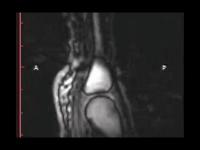

2005年加拿大的科研团队,利用专业设备,对手部进行了动态核磁共振扫描,他们发现,在手指关节之间充满了滑液,当手指受到牵拉时,滑液也会做出相应变化,这个过程中,滑液中会有气体出现,并在滑液中形成气泡。直到手指发出“咔”的声音,这个气泡都会存在。

因此,他们认为掰手指时响声的出现,并不是气泡破裂产生的,而是 和关节内空腔形成有关。

关节牵开时,可以看到关节腔里面有黑颜色的空腔形成

(摘自文献 Gregory N. Kawchuk, Jerome Fryer, Jacob L, et al. JaremkoReal-Time Visualization of Joint Cavitation,PLOS ONE,2015)